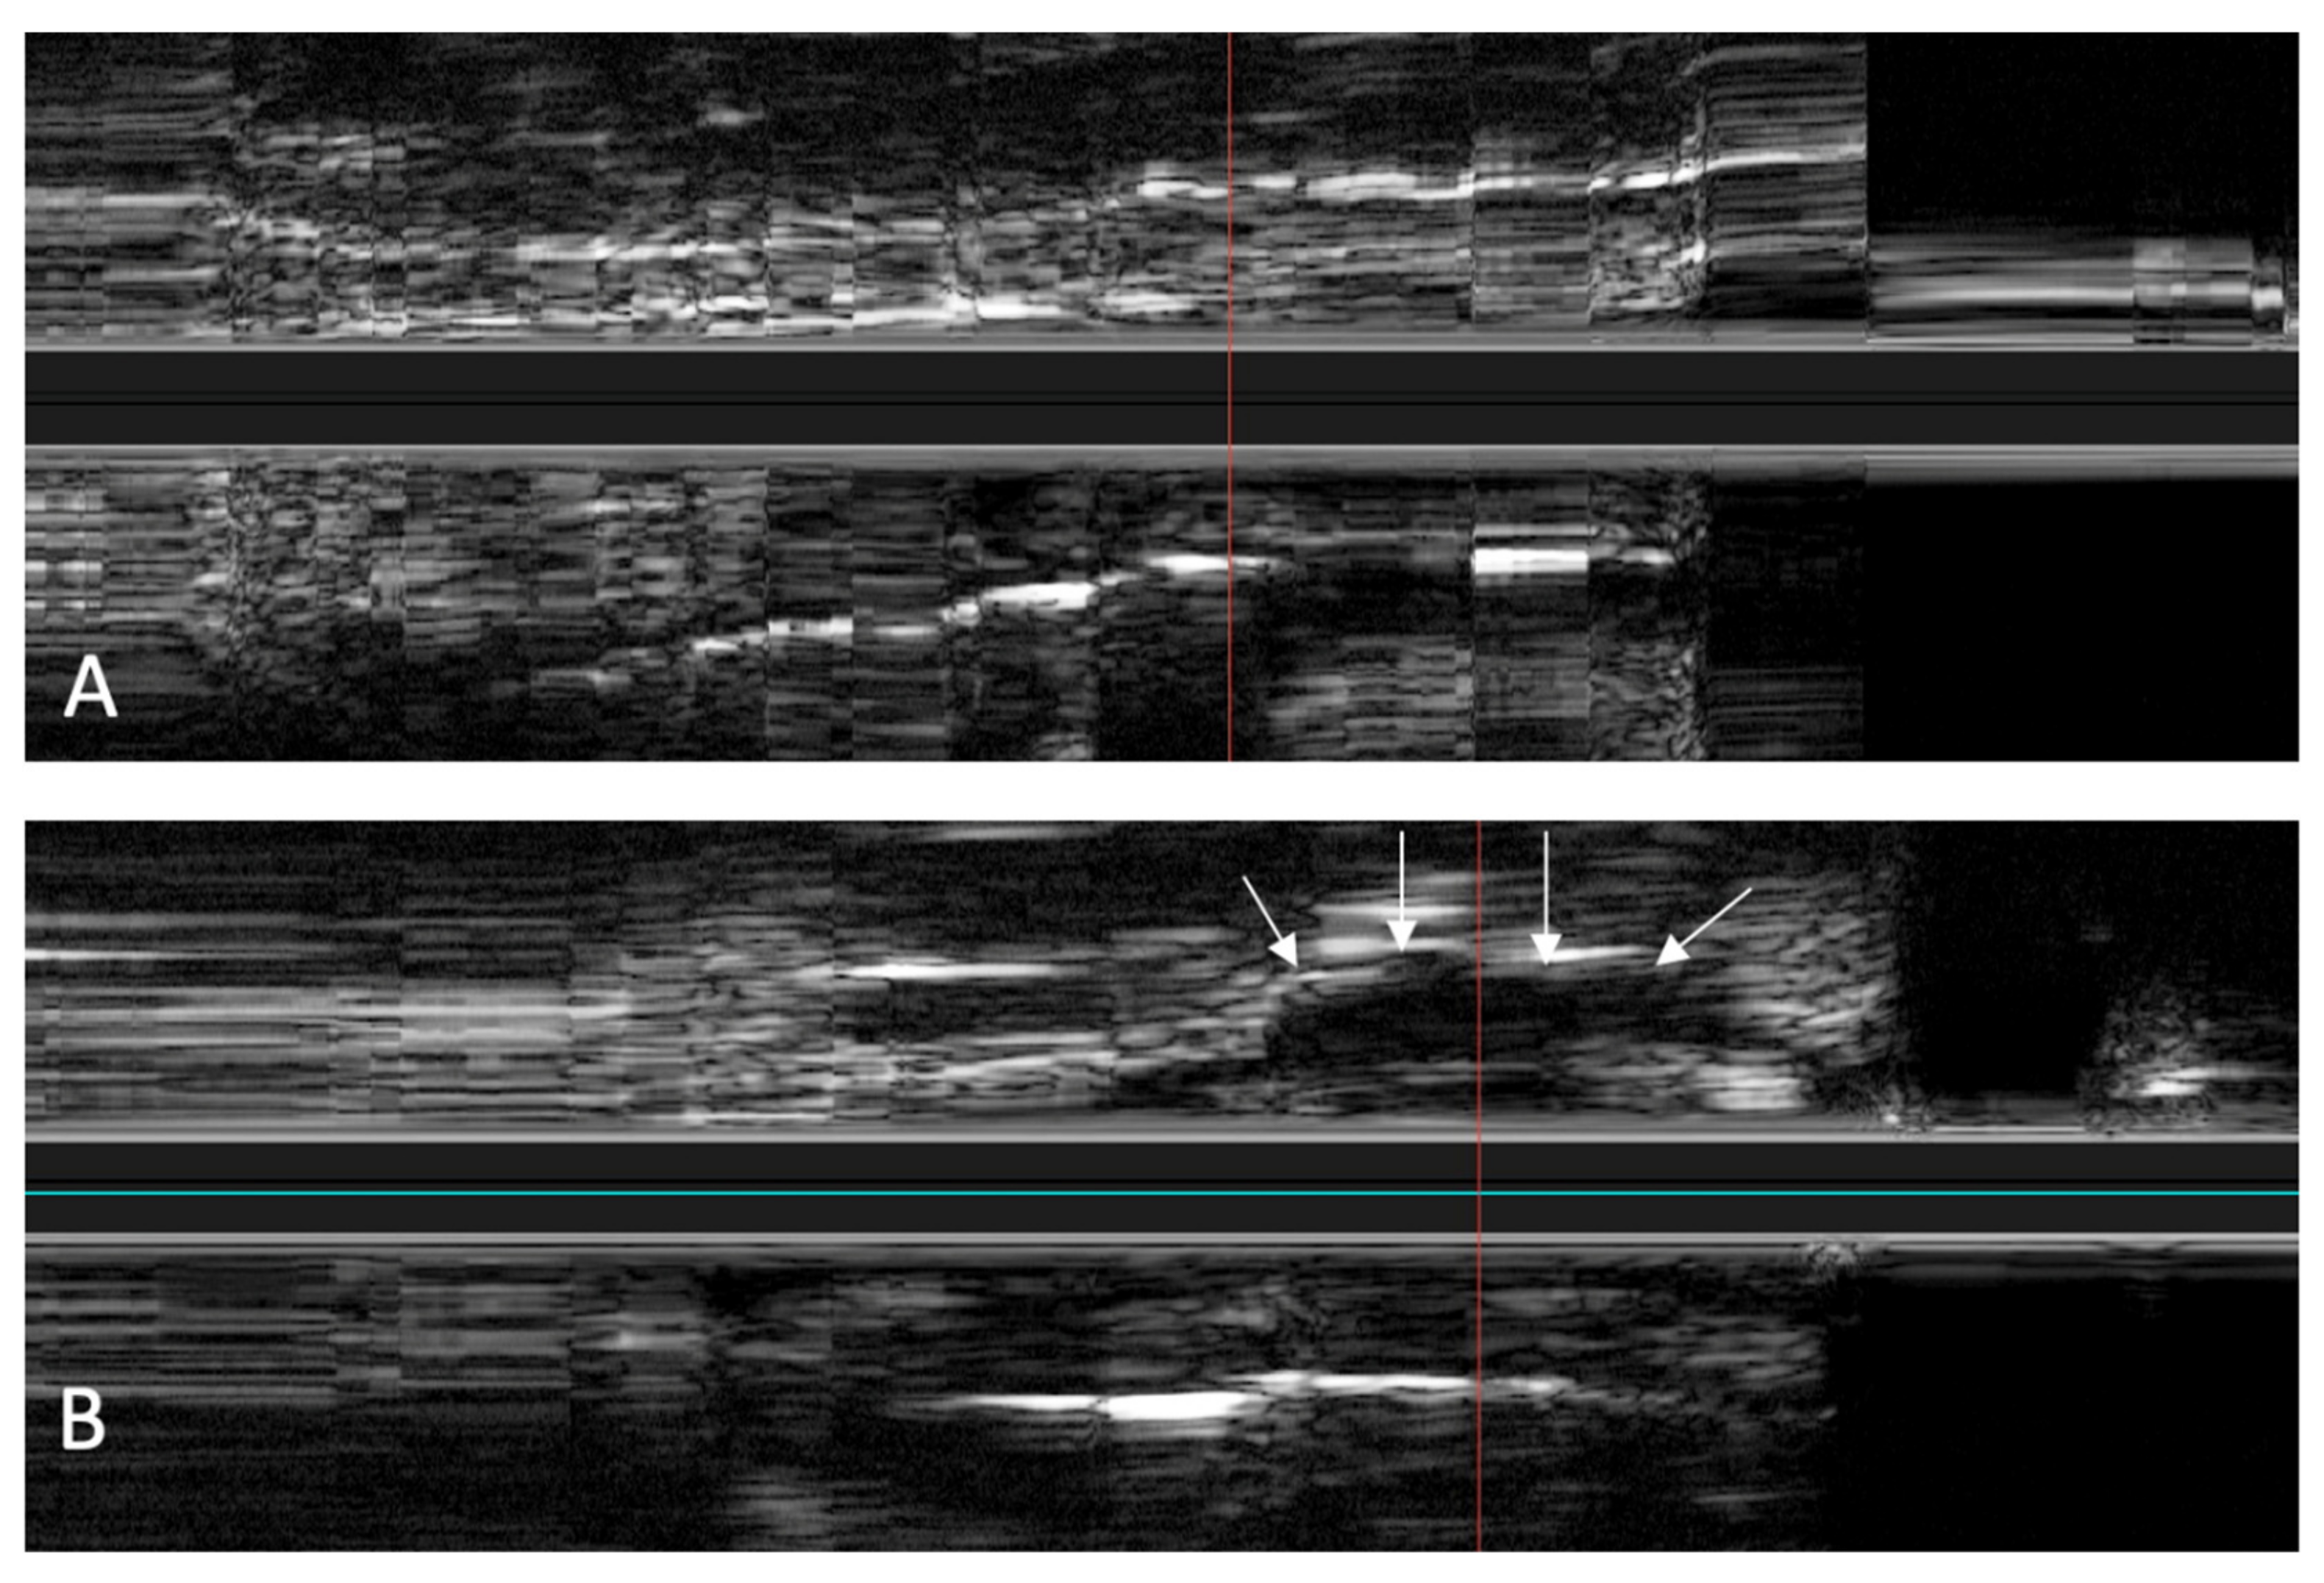

In the in vivo experiments, the IVUS catheter was inserted through the nostrils without any complications. During the insertion of the catheter and the scans, no injuries were detected. The scans were carried out without any problems, both before and after setting an HA depot with 2 mL in the tube course. In a direct comparison of the scans, the depot in the surrounding tissue could also be clearly identified, as shown in Figure 10.

Figure 10. In vivo longitudinal ultrasound image of the ET before (A) and after (B) placement of an HA depot. In (B), the HA depot is anechogenic next to the tubal lumen (marked by the white arrows).